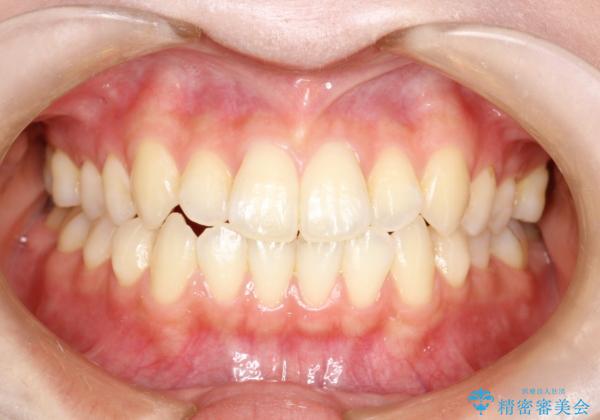

前歯のガタつき、下顎の前突感を治したい インビザライン矯正例

- 学生時代に矯正治療を経験されていましたが、その後の後戻りによる前歯の叢生・下顎の前突感を主訴に来院されました。叢生や口元の突出感が軽度であった為、非抜歯にて側方拡大やIPRを組み込んでインビザラインにて治療を計画しました。前歯部にクロスバイトがあり、治療途中に上顎前歯が下顎前歯を乗り越えなければならない時期もありましたが、患者様の協力的なマウスピース装着もあり、良好な配列を達成しました。上下左右の親知らずは、当院にて矯正開始前に抜歯しました。